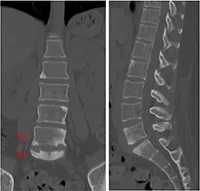

Vol.04[安静時の腰痛]

数年前より腰痛が出現し、年々悪化したため近医整形外科を受診したところ、CRP 1.31mg/dlと炎症反応上昇があり、腰椎CTでL5/S1を主とした椎体の硬化像やびらんを認めた。NSAIDs内服するも疼痛改善はなく、さらなる精査と治療のため脊椎関節炎の疑いで当院紹介となった。